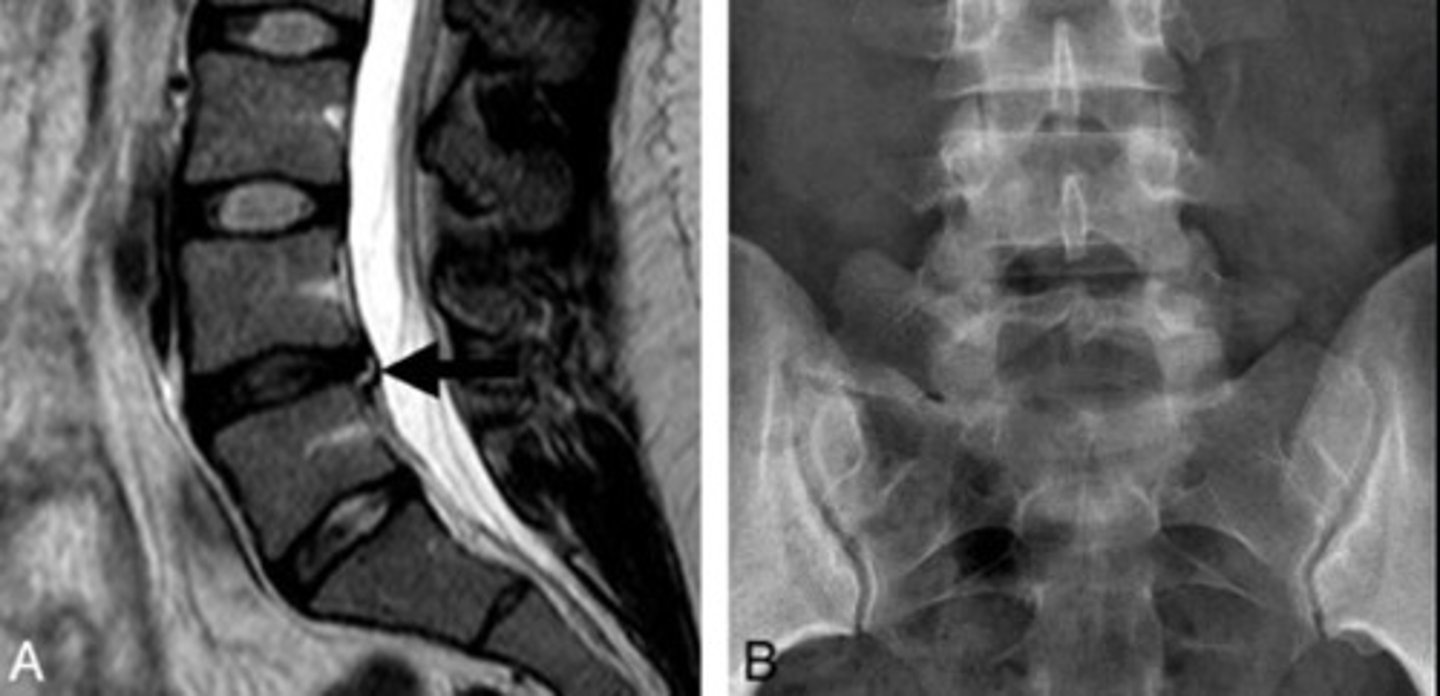

What is Bertolotti Syndrome?

Disc herniation with sacralization